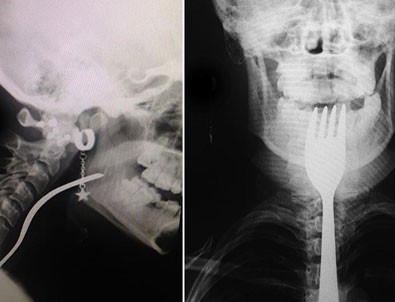

Dişini karıştırdığı çatal boğazına takıldı

Bursa'nın Orhangazi ilçesinde dişini karıştırdığı çatal boğazına girip takılan genç kız, hastaneye kaldırıldı.

Taksici babası İ.H.A. tarafından Orhangazi Devlet Hastanesine kaldırılan N.A, ilk müdahalenin ardından Uludağ Üniversitesi Tıp Fakültesi Hastanesine sevk edildi.

Burada yapılan müdahale sonucu genç kızın boğazına takılan çatal çıkarıldı.